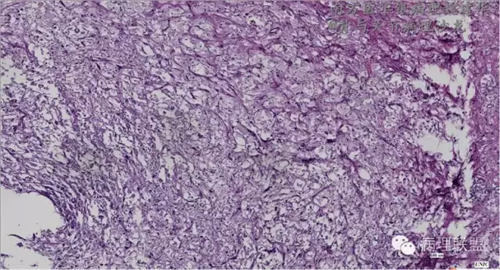

来源于组织细胞的相似性骨病ECD vs RDD 看图说话

病例由南方医华银病理魏建华提供,致谢。